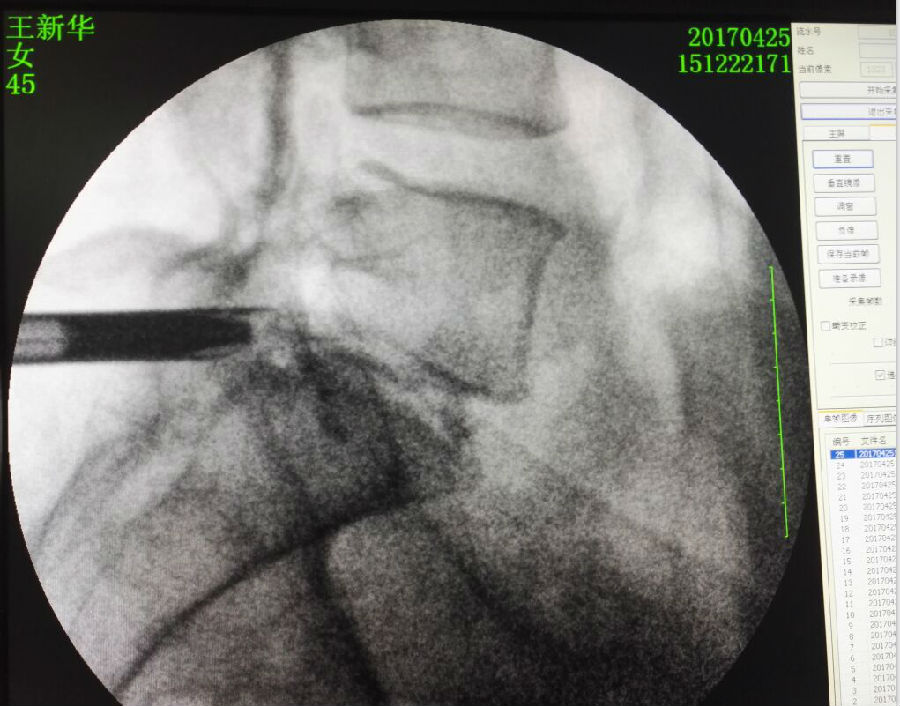

2017.4.25下午2时,在手术室护理人员配合下,疼痛康复科医生在患者背部切开17.5px切口,将直径15px工作套管放置于骶椎椎管内,在高倍放大镜下,利用髓核钳轻轻将突出物取出,同时利用等离子射频刀头修补住破裂的纤维环破裂口,2分钟后患者右下肢疼痛麻木感觉消失了。手术时间共计31分钟,手术切口缝合一针,患者卧床3天后即可出院回家休养。

淄博市妇幼保健院疼痛康复科已经熟练开展椎间孔镜下椎间盘疾患治疗技术,一般采用侧后路开口,此例患者因为脱出物过大甚至进入骶管腔,常用入路很难摘取到,经过反复研究影像资料,决定自椎板间通过黄韧带下缘进入骶管腔,这对手术者穿刺技术要求很高,既要达到突出物,又要避开椎管内的硬模囊和神经根。